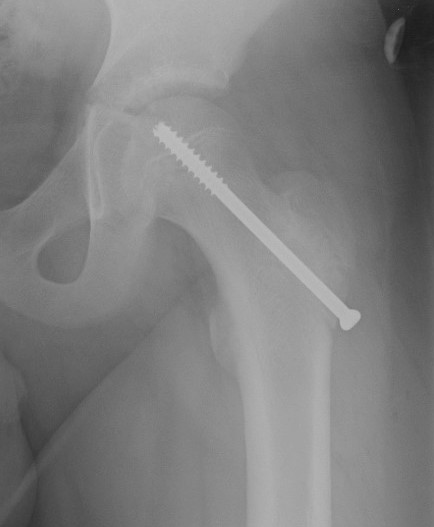

Intertrochanteric / Southwick

Technique

Removal anterolateral bone wedge below lesser trochanter

Valgising / flexion / internal rotation